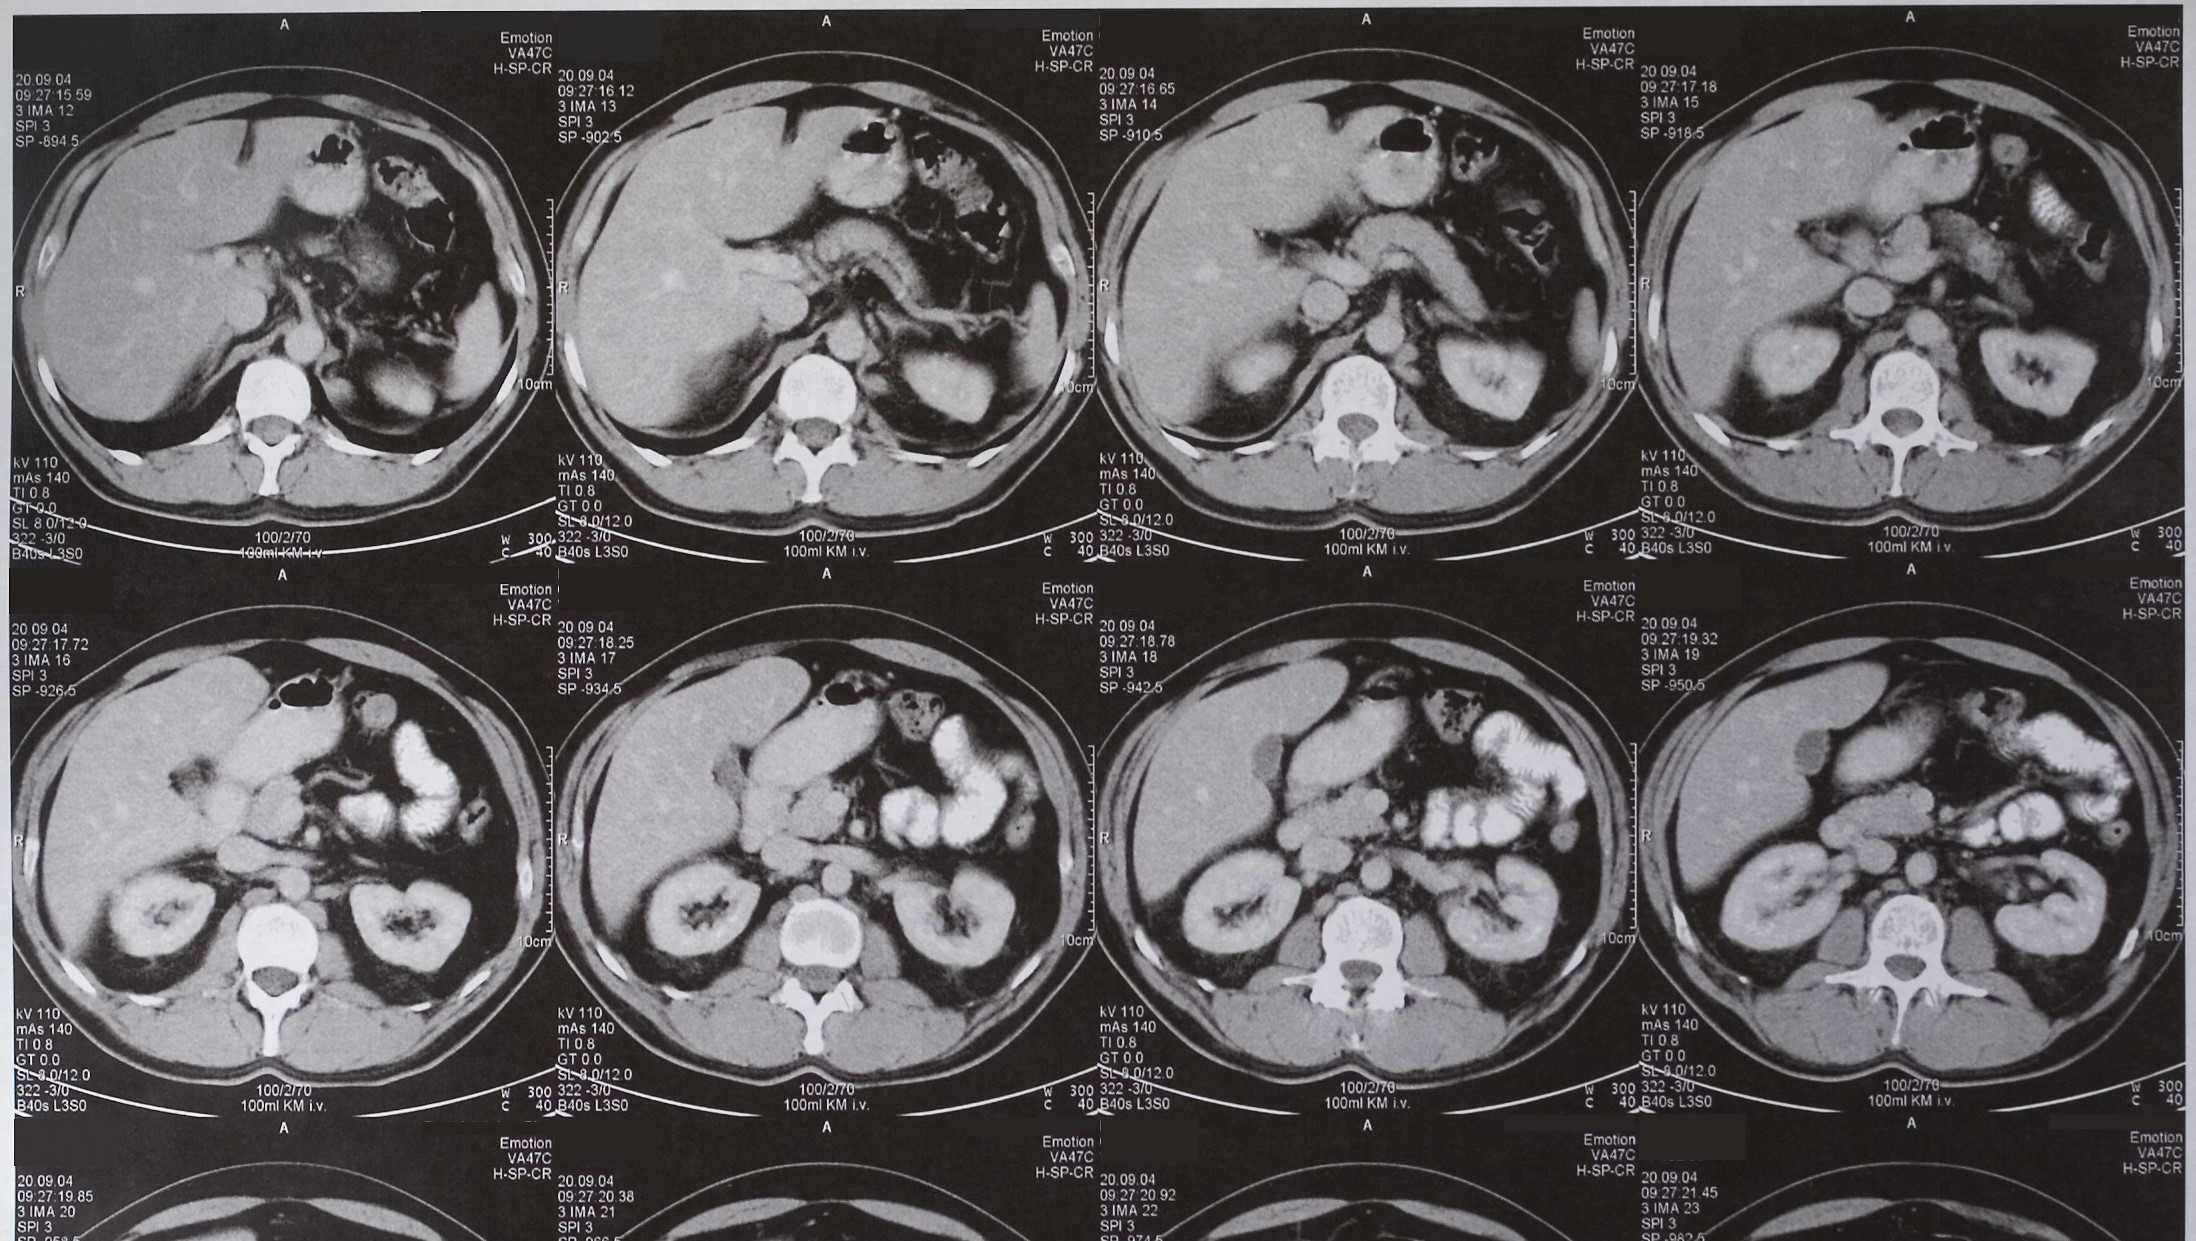

A CT scan of the abdomen and pelvis is a type of scan that uses special equipment to take pictures from different angles. These pictures are fed into a computer, which combines them to produce a series of cross sections or slices through the part of the pelvis being scanned. This creates a very detailed image of the abdomen and pelvis